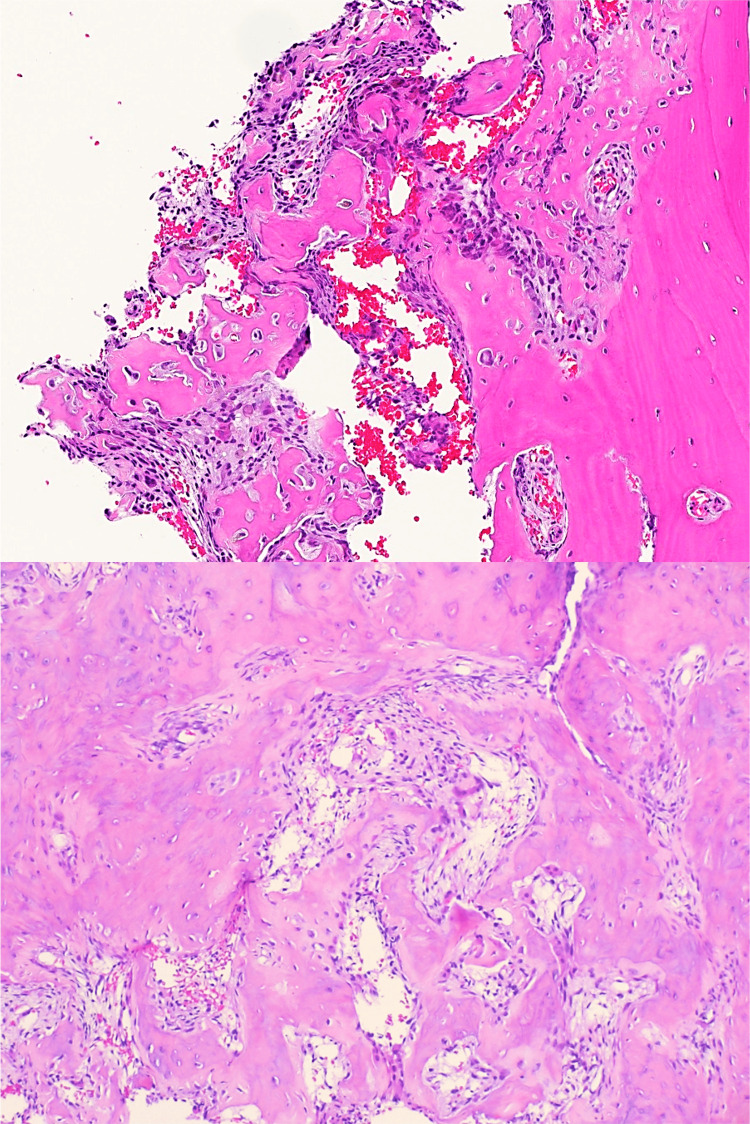

Pathology reports available for review showed bone-forming lesions composed of interlacing trabeculae and sheets of woven bone in a loose fibrovascular stroma with conspicuous osteoblastic lining and osteoclast-type giant cells, which is consistent with osteoid osteomas (Figure 5).

Figure 5. Histopathology images from one of the patients that were characteristic of osteoid osteoma.

Histopathology showing cancellous bone with a bone-forming lesion, composed of interlacing trabeculae and woven bone, with a notable lining of osteoblasts and scattered osteoclast-type giant cells.